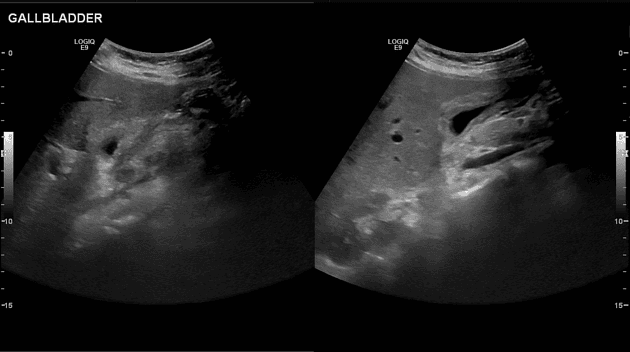

- Túi mật (gallbladder) co bóp.